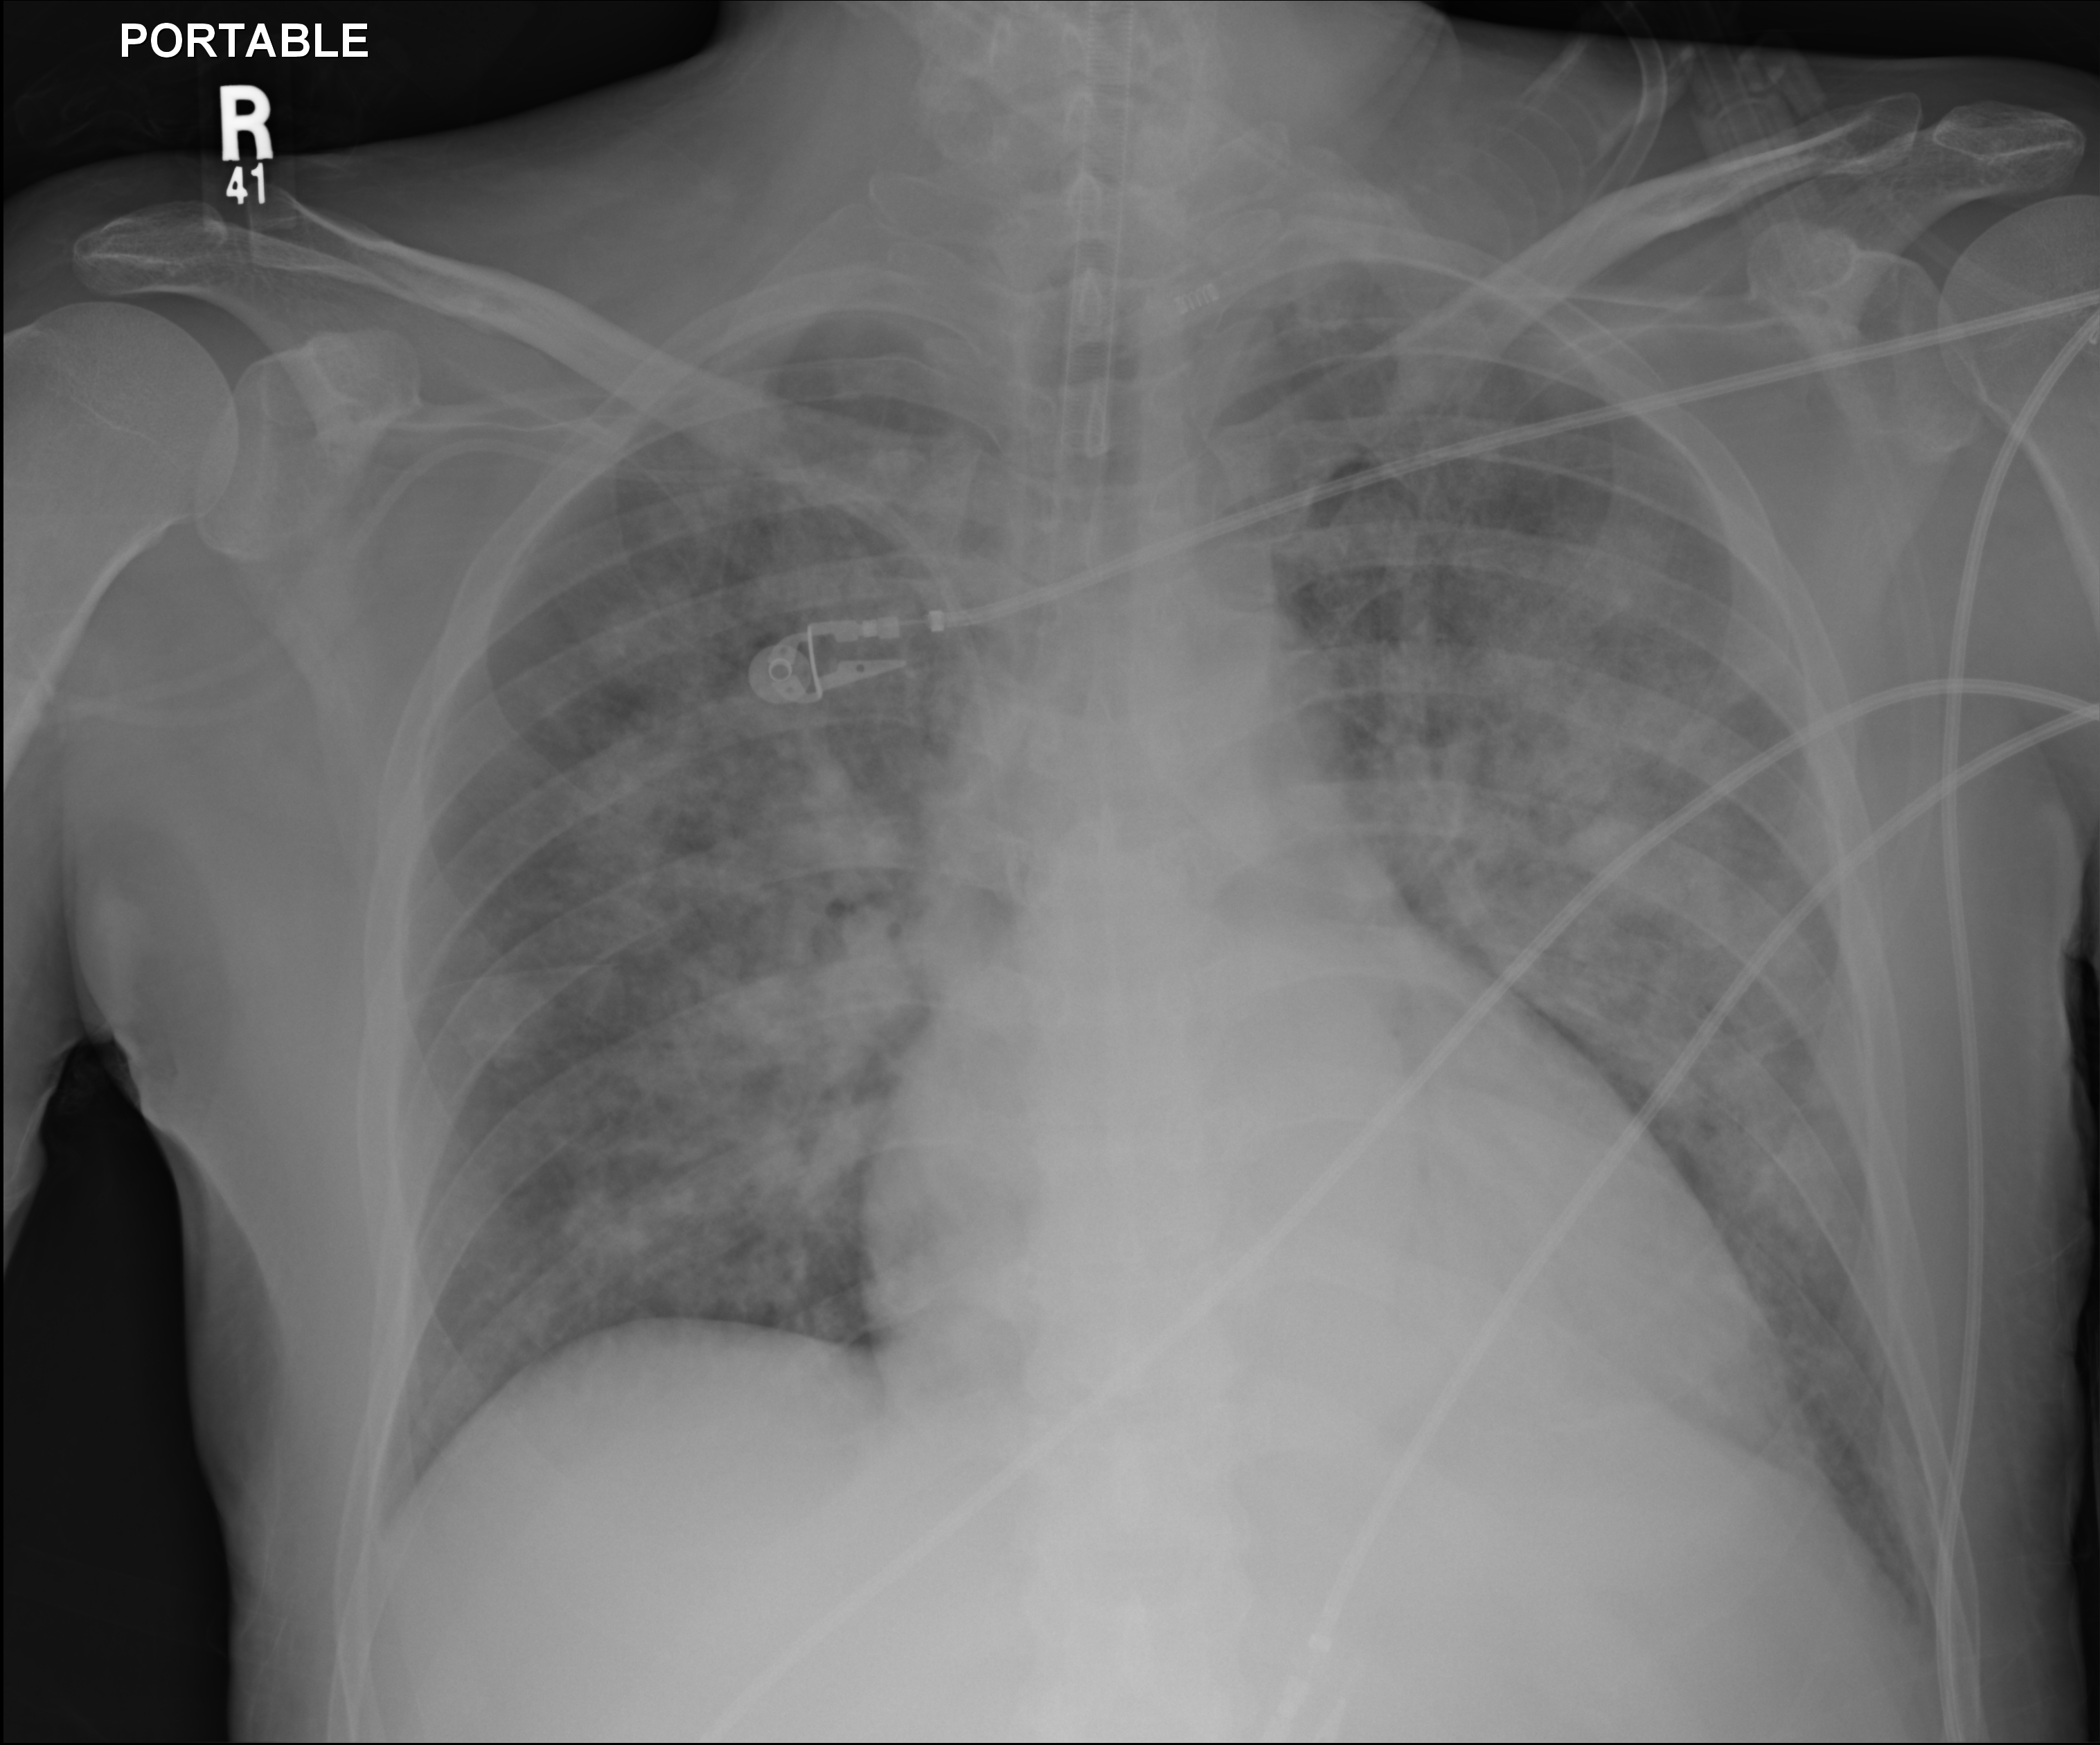

A couple of weeks ago a physician was examining me and noticed that I was no responding. He checked my legs and noticed I was bleeding all over. my stool was running and was full of blood. I was taken to ICU and the set of x-rays taken showed my LUNGS FULL OF BLOOD (refer to image one) The physician was very apologetic and told Issam and the family that there is nothing much he could do. The next day the x-rays showed my LUNGS FULLY CLEAR OF ANY FLUIDS AND VERY HEALTHY.  The same physician and many others were amazed, everyone was in awe. It was A MIRACLE CONFIRMED BY ALL !!! PRAISE THE LORD … MY JOURNEY CONTINUES …

” Today a lung expert evaluated Sami. He called me in amazement as to what has happened between March 5th and 6th in the ICU. He told me that he has never seen anything like this, and that this was a real miracle. Attached are copies of the X-rays before (March 5th) and after (March 6th). On the March 5th X-ray you see a white lung suggestive of a massive bleed / pneumonia on March 6th, you see clear lungs. The lung expert was amazed but after all the prayers, I was not. Praise the Lord. ”Â